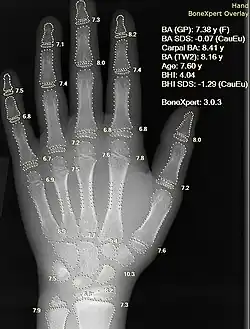

Die zwei gängigsten Methoden der Skelettalterbestimmung sind die Methoden nach Greulich und Pyle und die Methode nach Tanner und Whitehouse. Bei der Atlasmethode nach Greulich und Pyle wird das Röntgenbild der linken Hand mit Referenzbildern aus einem Atlas verglichen, das Skelettalter ergibt sich dann aus dem Bild, das der aktuellen Aufnahme am nächsten kommt. Wird die rechte Hand verwendet, ergibt sich kein signifikanter Unterschied im ermittelten Skelettalter.[2]

Aus vergleichenden Untersuchungen ist bekannt, dass die Skelettalterbestimmungen nach den beiden Methoden etwas differieren. Die Methode nach Tanner und Whitehouse gilt als präziser für deutsche Kinder, hier wird mit Hilfe vieler Referenzbilder einzelner Abschnitte der linken Hand ein Reifescore erstellt, aus dem sich dann anhand einer Tabelle das Knochenalter bestimmen lässt. Die Skelettalterbestimmung nach Tanner und Whitehouse ist somit aufwändiger.

Beide Methoden können automatisiert bestimmt werden.[3]

- ↑ H. H. Thodberg, S. Kreiborg, A. Juul, K. D. Pedersen: The BoneXpert Method for Automated Determination of Skeletal Maturity. In: IEEE Trans Medical Imaging. Vol. 28, 2009, S. 52–66.